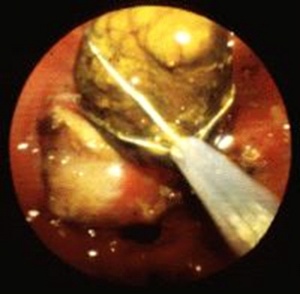

ב- ERCP אפשר להדגים את הכולדוכוס ואת האבן שבתוכו. אם מזהים את האבן, מבצעים פפילוטומיה להרחבת פתח הניקוז. מחדירים סל דרך תעלת האנדוסקופ, לוכדים את האבן ושולפים אותה החוצה. אם האבן גדולה, אפשר לשבור אותה בעזרת הסל ולהוציא את חלקיה (תמונה 3.8).

| תמונה 3.8: הוצאת אבנים דרך הפפילה על-שם ואטר ב-ERCP. | |